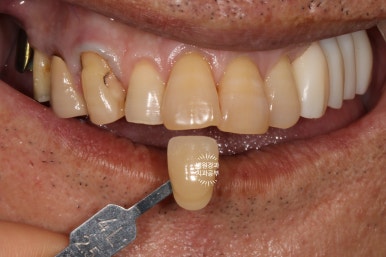

최대한 자연스러운 색상으로 제작해드리기 위하여, 남아있는 자연치인 위턱 앞니들과 유사한 색으로 임플란트 크라운을 제작해드리기로 하였습니다.

저희가 가지고 있는 VITA Shadeguide 기준으로 4L 2.5의 색상으로 측정되었네요.

다소 어둡고 yellowish한 느낌의 치아색상입니다.